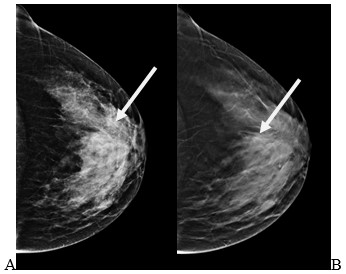

Что такое маммография: важность, процесс и результаты